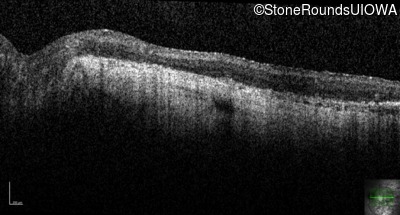

Optical Coherence Tomography - Left - Hand Motion

Exemplar / OCT Stack